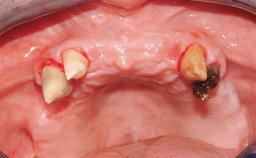

Immediate Loading of Eight Implants in the Maxilla and Six Implants in the Mandible and Final Restoration with Three-Unit and Four-Unit FDPs

German Gallucci, Jean-Pierre H Bernard, Urs C Belser

Extensive scientific evidence has confirmed that immediately loaded implants with fixed full-arch provisional restorations can osseointegrate with success rates similar to conventionally or delayed loaded implants. A number of immediate-provisionalization techniques for edentulous jaws have been described. Some protocols differ when it comes to prefabricated provisional templates versus complete denture conversion; intrasurgical impressions versus direct relining; and cemented versus screw-retained provisional restorations. In this context, complete-denture conversion has been proposed for either intrasurgical impressions or direct relining. Another possibility is the utilization of a prefabricated provisional to be adapted either in the mouth (by direct relining) or in the laboratory (on a working model obtained from an intrasurgical impression).

Case Type Edentulous Maxilla

Defining Characteristics Fully edentulous upper jaw to be rehabilitated with four or more implants